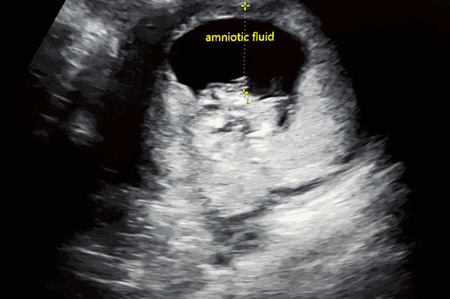

Jika tidak ada cairan ketuban yang terukur di sekitar bayi Anda, kondisi ini disebut anhidramnion. Oligohidramnion dan anhidramnion hanya dapat didiagnosis setelah pemindaian ultrasonografi (USG).

Kisaran level air ketuban yang normal sedikit berubah bergantung pada usia dan tahap kehamilan. Jika saat pemeriksaan cairan ketuban, ada area. yang memiliki kedalaman kurang dari 2cm, kondisi ini dianggap lebih rendah dari normal.

Untuk memastikan kondisi air ketuban, Anda perlu melakukan ultrasound untuk mengevaluasi ukuran janin dan level cairan ketuban, karena keduanya bisa memengaruhi ukuran perut ibu hamil.

Melansir Cleveland Clinic, petugas kesehatan mengukur jumlah cairan ketuban di rahim selama beberapa kali selama kehamilan dengan menggunakan ultrasound. Jika jumlahnya kurang dari yang direkomendasikan sesuai dengan usia kehamilan dan umur janin, maka kemungkinan Anda mengalami oligohidramnion.

- Amniotic fluid index (AFI). Proses membagi rahim menjadi empat bagian dan mengukur kantong terdalam dari setiap bagian. Ukuran keempat bagian ditambahkan untuk mendapatkan AGI. Normal AFI adalah lebih dari 5 sentimeter.

- Maximum vertical pocket (MVP). Proses melibatkan mengukur satu kantong terdalam dari cairan ketuban. Idealnya, MVP harus kurang dari 2 cm.

Air ketuban dianggap normal jika berwarna bening kekuningan, tidak berbau, dan volumenya sesuai dengan usia kehamilan. Anda bisa memantaunya melalui pemeriksaan USG.